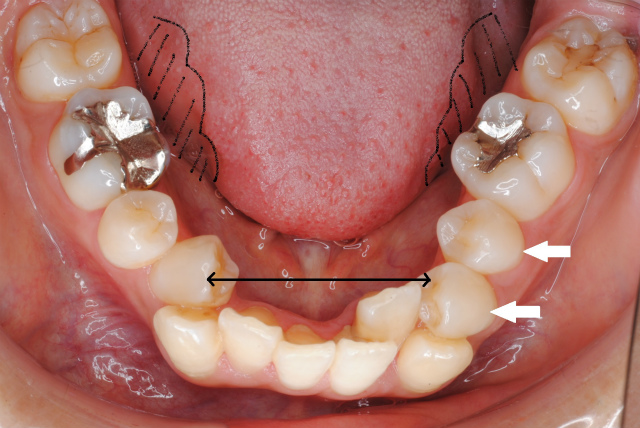

舌体のサイドに歯の痕がくっきりとついている場合は、舌が大きい場合もありますが、下あごの小・大臼歯が内側に倒れて歯列の幅が狭くなっている場合も多いのです。さらには個々の小・大臼歯が上から常に舌に押され続けることで前方に倒されてしまって、前歯にしわ寄せがきて歯並びが乱れることが考えられます。(左下図の白矢印)

さらには、舌体は常時下顎の歯列内に収まったままで殆ど動いていない場合も考えられます。

初診 下顎の歯並びの状態